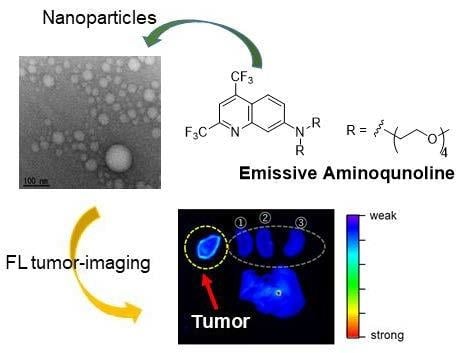

Fluorescence Tumor-Imaging Using a Thermo-Responsive Molecule with an Emissive Aminoquinoline Derivative

:1. Introduction

2. Results and Discussion

2.1. Synthesis

2.2. Solubility for Aqueous Solution

2.3. Self-Assembly Behavior

2.6. Tumor-Imaging with TFMAQ-diEg4

4. Conclusions